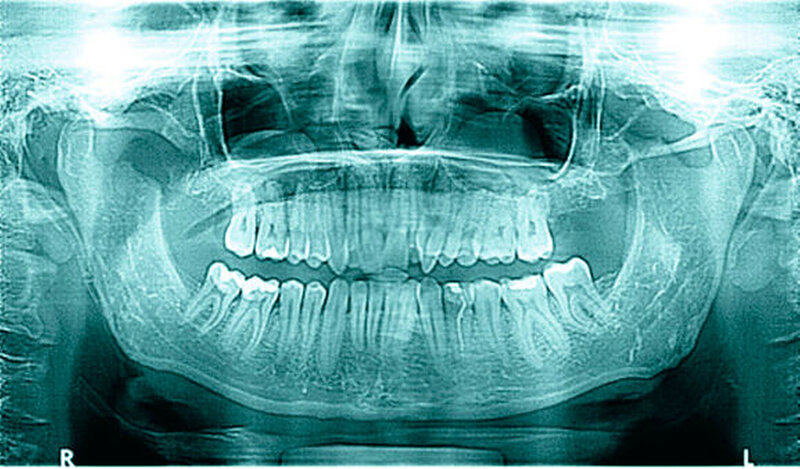

In der erweiterten radiologischen Diagnostik mittels CT zeigten sich symmetrisch angelegte Kiefergelenke beidseits ohne arthrotische Veränderungen oder signifikante Deformierungen. Ein Hinweis auf Luxation ergab sich nicht. In den axialen Schichten stellten sich beide Proc. coronoidei bis hoch in die jeweilige Fossa temporalis dar. In der 3-D-Rekonstruktion imponierten die hyperplastischen Proc. coronoidei beidseits. Diese ragten weit über die Jochbögen hinaus und schränkten dadurch die Mundöffnung ein (Abbildung 3).